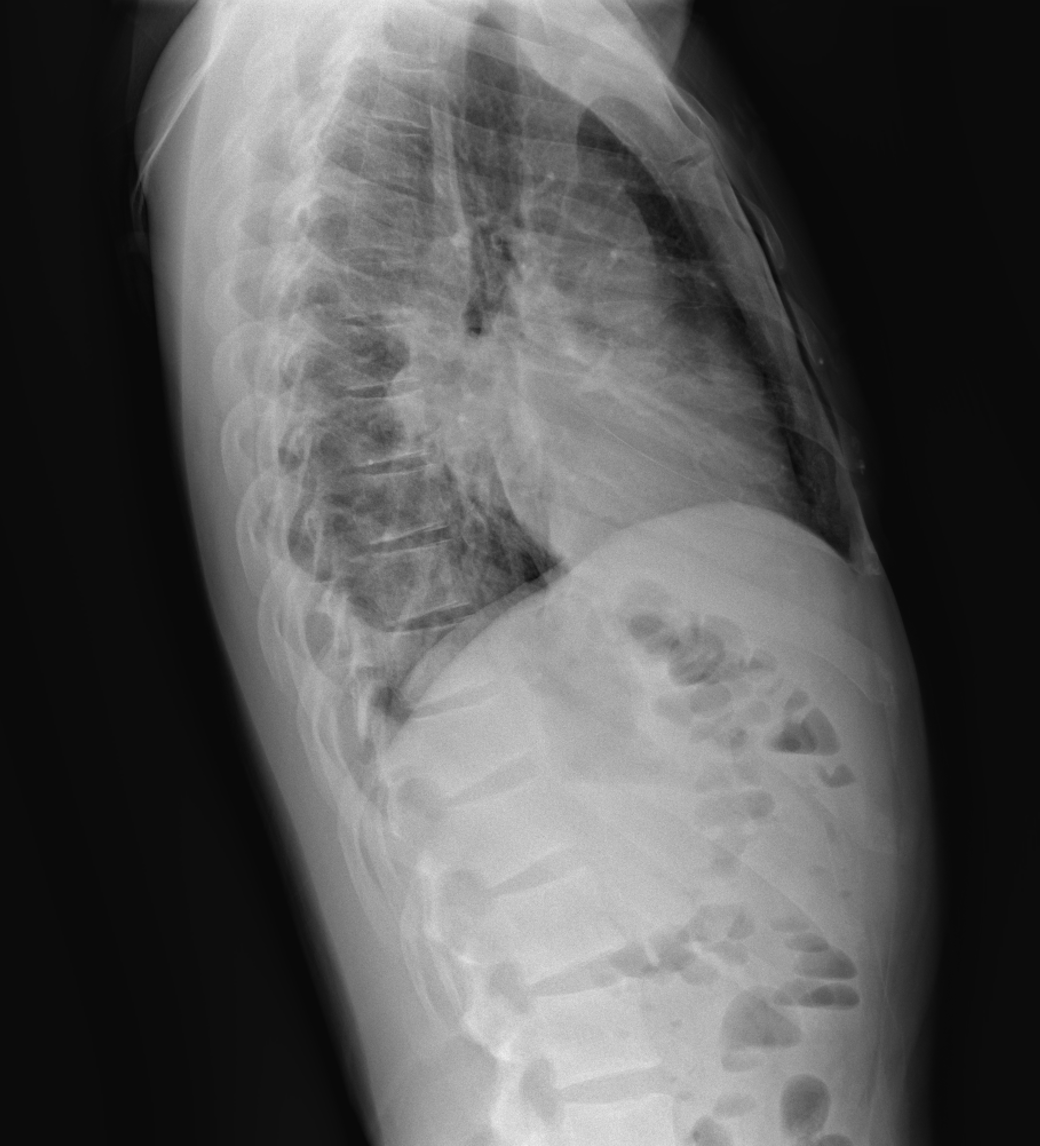

Exploración: buen estado general, eupneico, afebril, constantes vitales estables. Saturación de oxígeno 100%. Sin trabajo respiratorio. Auscultación pulmonar objetiva hipofonesis en lóbulo inferior izquierdo (LII) y crepitantes dispersos. No edemas.

Consolidación en LII y derrame pleural izquierdo a estudio.

Ingreso en Neumología, donde realizan toracocentesis y bioquímica líquido pleural, con evidencia de exudado mononuclear y ADA 80 U/L. Se realiza PCR líquido pleural positivo para M. tuberculosis. Antigenuria, hemocultivo y serología de virus negativos. Cultivo de esputo no representativo. Se diagnostica de tuberculosis pleuropulmonar izquierda e inician tratamiento antituberculoso con controles radiológicos posteriores.

La tuberculosis pleural es una forma frecuente de tuberculosis extrapulmonar, manifestada como derrame pleural aislado o asociando lesiones pulmonares (tuberculosis pleuropulmonar). Su diagnóstico requiere demostrar M. tuberculosis en líquido o biopsia pleural, aunque ADA e interferón gamma ofrecen alta sensibilidad y especificidad clínica. Además de la clínica y radiografía torácica, la ecografía aporta ventajas en Urgencias, permitiendo detectar derrame o engrosamiento pleural y septaciones, así como guiar procedimientos invasivos y monitorizar manejo y evolución clínica.